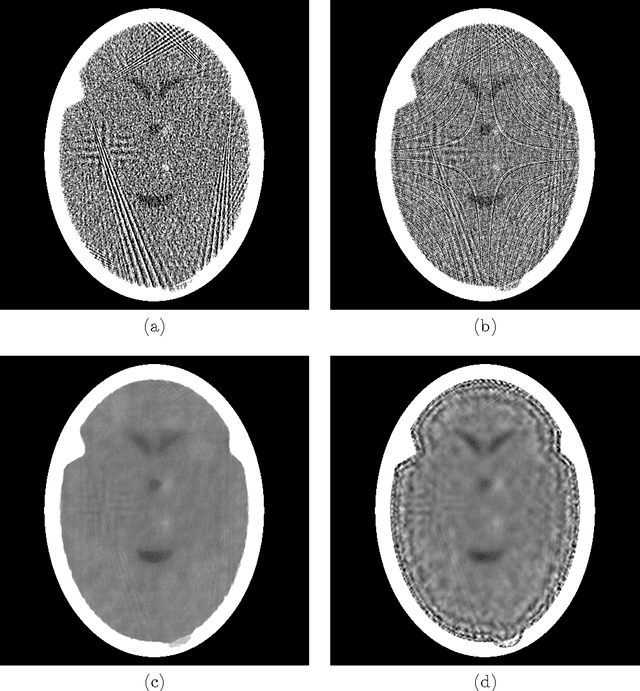

To reduce the x-ray dose in computerized tomography (CT), many constrained optimization approaches have been proposed aiming at minimizing a regularizing function that measures lack of consistency with some prior knowledge about the object that is being imaged, subject to a (predetermined) level of consistency with the detected attenuation of x-rays. Proponents of the shearlet transform in the regularizing function claim that the reconstructions so obtained are better than those produced using TV for texture preservation (but may be worse for noise reduction). In this paper we report results related to this claim. In our reported experiments using simulated CT data collection of the head, reconstructions whose shearlet transform has a small $\ell_1$-norm are not more efficacious than reconstructions that have a small TV value. Our experiments for making such comparisons use the recently-developed superiorization methodology for both regularizing functions. Superiorization is an automated procedure for turning an iterative algorithm for producing images that satisfy a primary criterion (such as consistency with the observed measurements) into its superiorized version that will produce results that, according to the primary criterion are as good as those produced by the original algorithm, but in addition are superior to them according to a secondary (regularizing) criterion. The method presented for superiorization involving the $\ell_1$-norm of the shearlet transform is novel and is quite general: It can be used for any regularizing function that is defined as the $\ell_1$-norm of a transform specified by the application of a matrix. Because in the previous literature the split Bregman algorithm is used for similar purposes, a section is included comparing the results of the superiorization algorithm with the split Bregman algorithm.